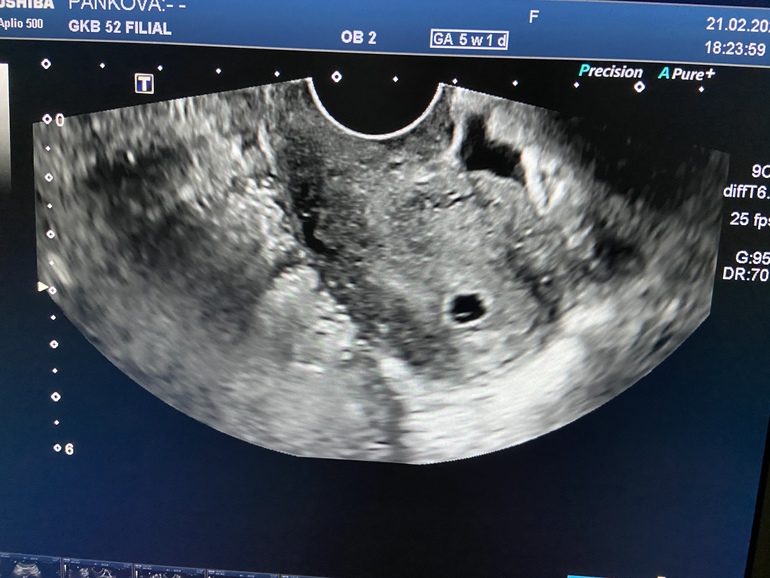

Результаты: УЗИ, КТГ, доплера, скринингаЗдравствуйте, подскажите нельзя ли предполагать что ПЯ не одно? Или подскажите кто знает, что за чёрные пятнышки рядом) 5 недель)

Точно Одно, но всегда еще есть вероятность что может раздвоится 👍 но это такая редкость!

У вас одно ПЯ. Остальное это сосуды, сосудистые вкрапления и маточная структура